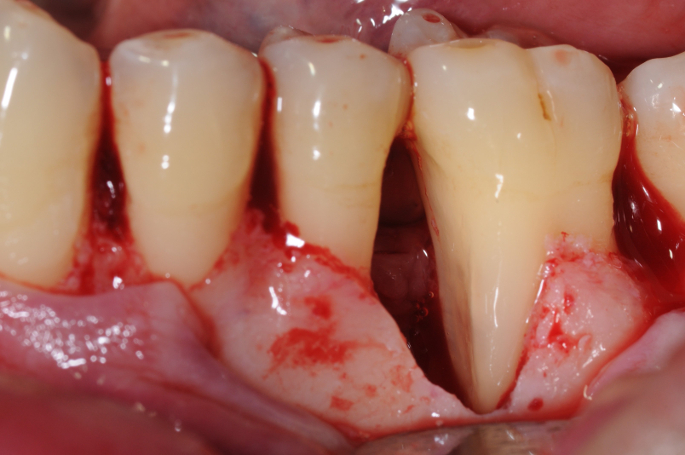

Fotos dos casos clínicos